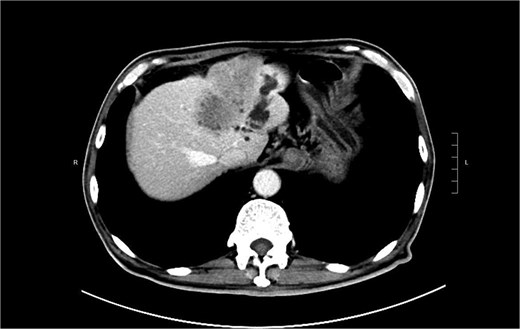

A 74-year-old man who had history of hypertension and diabetes mellitus presented with upper gastrointestinal bleeding. Upper endoscopy revealed deformed pylorus and a 1 cm deep ulcer at anterior wall of first part of duodenum (Fig. 1). Computed tomography (CT) revealed a 4.8 cm exophytic hypoenhancing mass at segment 4a of liver with dilated left intrahepatic duct (Fig. 2). There was aerobilia suggestive of choledochoduodenal fistula. There was also suspicion of diaphragm invasion. Serum carcinoembryonic antigen (CEA) was elevated to 83ug/L while alpha-fetoprotein (AFP) was normal. Both the hepatitis B surface antigen and anti-hepatitis C antibody were negative. Positron emission tomography (PET) confirmed a hypermetabolic liver tumor but no distant metastasis. The clinical diagnosis was ICC with suspected duodenal and diaphragmatic invasion. The patient was offered radical resection for tumor.

CT showing showing an exophytic hypoenhancing mass at left liver with dilated left intrahepatic duct.